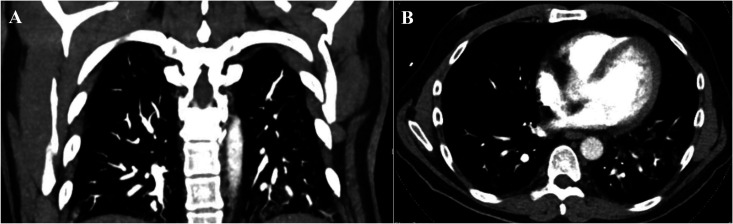

We describe the case of a gentleman with relapsing-remitting multiple sclerosis and chronic lymphocytopenia secondary to treatment with fingolimod who presented with disseminated histoplasmosis after receiving the third dose of the Moderna coronavirus disease 2019 (mRNA-1273) vaccine. Following the vaccination the patient noted fatigue which worsened over time along with gradual weight loss. A few months later he noted low-grade fever and finally shortness of breath. A diagnosis of disseminated histoplasmosis was performed based on urine, blood, and imaging data. He responded well to prolonged antifungal treatment. Fingolimod was discontinued and replaced with glatiramer acetate. He has been clinically stable until the time of this report, 33 months following symptom onset.